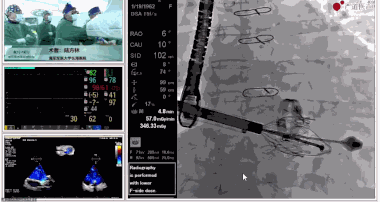

▲瓣膜植入后釋放的過程

▲瓣膜植入后三維超聲影像

▲瓣膜植入后右心室造影

在手術直播中瓣膜植入過程不到10分鐘,手術獲得圓滿成功,充分體現(xiàn)徐志云、陸方林團隊技術精湛,團隊協(xié)作默契及器械的優(yōu)越性。